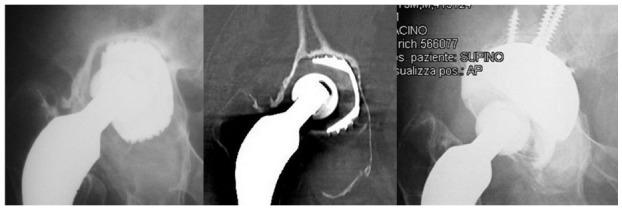

使用多孔钽组件的髋臼翻修术:一项随访5至10年的回顾性研究。

Acetabular revisions using porous tantalum components: A retrospective study with 5-10 years follow-up.

To evaluate the clinical and X-ray results of acetabular components and tantalum augments in prosthetic hip revisions.

Fifty-eight hip prostheses with primary failure of the acetabular component were reviewed with tantalum implants. The clinical records and X-rays of these cases were retrospectively reviewed. Bone defect evaluations were based on preoperative CT scans and classified according to Paprosky criteria of Radiolucent lines and periprosthetic gaps; implant mobilization and osteolysis were evaluated by X-ray. An database was created and statistical analyses were performed with SPSS software (IBM SPSS Statistics for Windows, version 23.0). Statistical analyses were carried out using the Student's test for independent and paired samples. A value of < 0.05 was considered statistically significant and cumulative survival was calculated by the Kaplan-Meier method.

RESULTS

The mean follow-up was 87.6 ± 25.6 mo (range 3-120 mo). 25 cases (43.1%) were classified as minor defects, and 33 cases (56.9%) as major defects. The preoperative HHS rating improved significantly from a mean of 40.7 ± 6.1 (range: 29-53) before revision, to a mean of 85.8 ± 6.1 (range: 70-94) at the end of the follow-up (Student's test for paired samples: < 0.001). Considering HHS only at the end of follow-up, no statistically significant difference was observed between patients with a major or minor defect (Student's test for independent samples: > 0.05). Radiolucent lines were found in 4 implants (6.9%). Postoperative acetabular gaps were observed in 5 hips (8.6%). No signs of implant mobilization or areas of periprosthetic osteolysis were found in the x-rays at the final follow-up. Only 3 implants failed: 1 case of infection and 2 cases of instability. Defined as the end-point, cumulative survival at 10 years was 95% (for all reasons) and 100% for aseptic loosening of the acetabular component.

CONCLUSION

The medium-term use of prosthetic tantalum components in prosthetic hip revisions is safe and effective in a wide variety of acetabular bone defects.